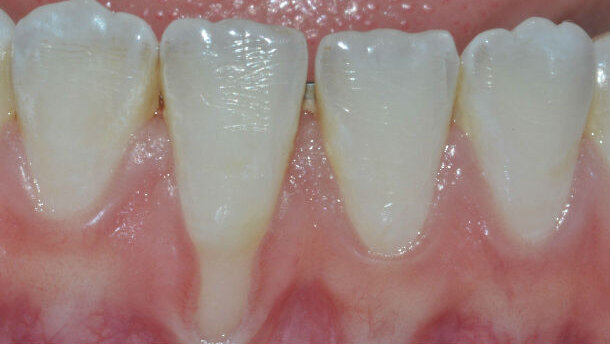

Le recessioni gengivali, patologiche esposizioni radicolari con migrazione apicale del tessuto marginale (Fig. 1), sono largamente diffuse. Esse costituiscono un problema in termini di durata degli elementi dentari otre che estetici e, talora, di ipersensibilità dentale.